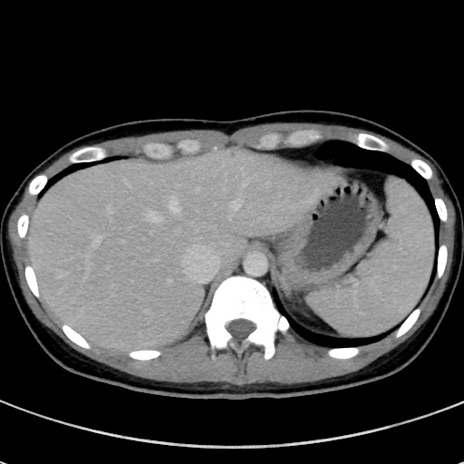

症例17(横断像)

【症例】20歳代女性

【主訴】嘔吐、下腹部痛

【現病歴】昨日夕食後に嘔吐し下腹部痛が出現。本日になっても嘔吐持続し改善しないため来院。

【身体所見】意識清明、BT 37.2℃、BP 108/67mmHg、腹部:平坦、やや硬、下腹部正中から右にかけて圧痛あり、反跳痛軽度あり、tapping pain(+)。

【データ】WBC 13600、CRP 14.94